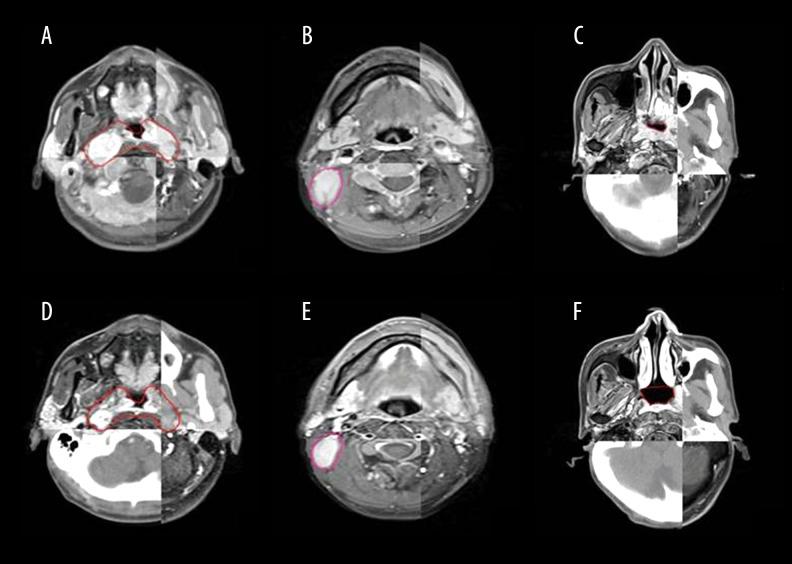

BACKGROUND Gemcitabine plus cisplatin (GP) is a novel regimen of induction chemotherapy (IC) for treating locoregional advanced nasopharyngeal cancer (NPC). This retrospective study aimed to compare the efficacy of GP and TP (paclitaxel plus cisplatin) regimens in tumor volume reduction after IC. MATERIAL AND METHODS Between January 2014 and July 2017, 44 patients with III-IVB stage NPC received GP IC followed by concurrent chemoradiotherapy. These patients were matched with 44 patients receiving TP IC according to clinical characteristics. The gross tumor volume of the primary site and positive lymph nodes were delineated by magnetic resonance imaging before and after IC, as well as the nasopharyngeal air cavities. The changes in tumor volume and nasopharyngeal air cavity after IC were calculated and compared between the 2 groups. Treatment toxicities and early survival outcomes were also reported. RESULTS There were no differences in the initial tumor volume and nasopharyngeal cavity between the 2 groups. The volume changes after IC for the primary site, lymph nodes, and nasopharyngeal cavity were 31.4 (range, -0.97-75.8), 4.68 (range, -7.08-22.06), and 2.62 (range, 0.1-7.63) mL for GP and 23.36 (range, -59.14-83.58), 4.7 (range, -11.21-48.61), and 1.47 (range, -2.47-6.17) mL for TP, respectively. All comparisons favored the GP regimen. The toxicities of the 2 regimens were comparable and no survival differences were observed at follow-up (median, 18.7 months). CONCLUSIONS Changes in the tumor volume and nasopharyngeal air cavity showed that the GP regimen was significantly more effective than the TP regimen in tumor burden reduction. However, whether the advantages of GP can translate into survival benefits requires further investigation.

2014 年 1 月至 2017 年 7 月,44 例 III-IVB 期 NPC 患者接受 GP IC 治疗,随后行同期放化疗。这些患者根据临床特征与 44 例接受 TP IC 治疗的患者相匹配。在 IC 前后,通过磁共振成像描绘原发部位和阳性淋巴结的大体肿瘤体积以及鼻咽腔。计算并比较两组患者 IC 后肿瘤体积和鼻咽腔的变化。还报告了治疗毒性和早期生存结果。